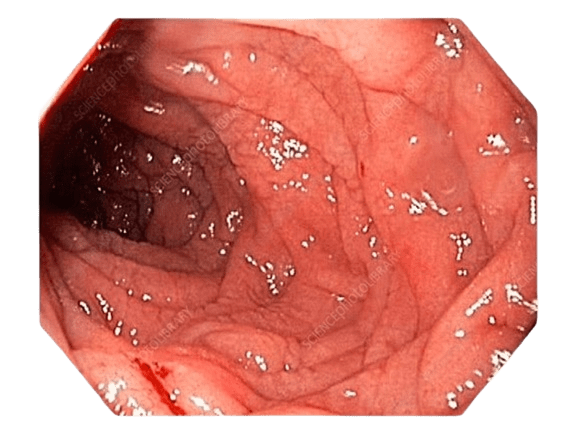

This is the beginning of the small intestine and most commonly affected by acidity and ulcer.

It also may be involved in certain cancers of upper GI tract.

Bloating, fullness of abdomen, burping, vomiting, pain or burning in upper abdomen mostly on empty stomach after consumption of chillies,

spices or heavy meals occurring at times during sleep are the symptoms related to duodenum.

Duodenum - Chronic Ulcer

Duodenum - Chronic Ulcer with Bleeding

Vomiting of blood due to ulcer, narrowing of duodenum due to ulcer or cancer can be very effectively treated by gastroscopy.